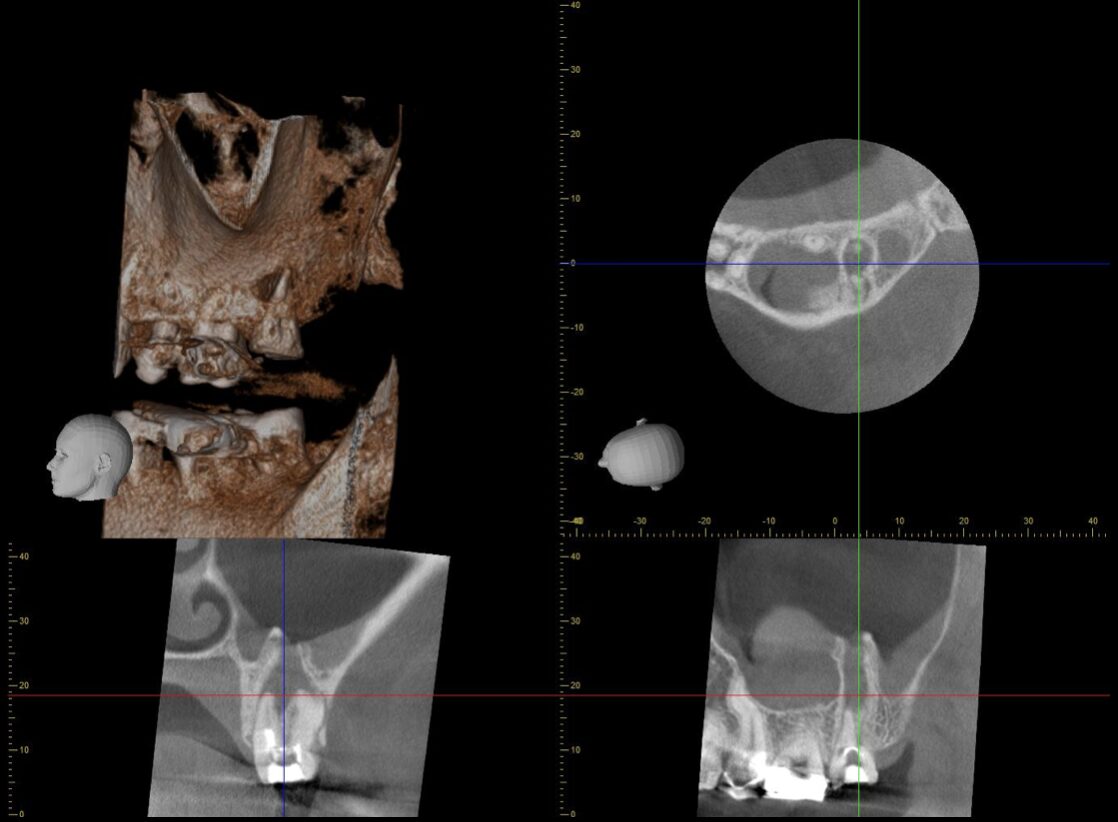

口腔内診査とCTから、根尖性歯周炎と診断。根管治療の再治療が必要です。

CTの所見では、根尖周囲の病変は大きく成長し、上顎洞粘膜を持ち上げ、さらに上顎洞粘膜の肥厚も認めます。病変と上顎洞は一部交通している状態。

治療をスタートしてみると、根管内は著しく感染していました。

また、見逃された根管を認めました。

根の中は、形、本数、位置に個人差があり、全く同じ構造の歯はほとんどありません。

前医での治療に不備があったというよりも、今回のようにイレギュラーな位置での根管は、マイクロスコープやCTや専門器具がないと、発見することが不可能なことが多いです。

また、イレギュラーな根管を持つ歯は、分岐の位置や根の形もイレギュラーなことが多く、さらに隠れた道がないかを探索し、それらを拡大、洗浄する必要がありました。

根尖孔が大きく開いていたので、その部分はMTAセメントで封鎖し、他の部分はガッタパーチャーで根管充填を行いました。

術後3ヶ月のCTで、治癒が認められました。

- 今回のような、複雑な形の根管を有する歯は、見逃した根管を見つけることができたとしても、器具が届かないエリアが存在することも多く、根管治療だけで治癒ができない場合があります。

もし、治癒が期待できない場合は、意図的再植術という処置へ移行することを話し合いました。